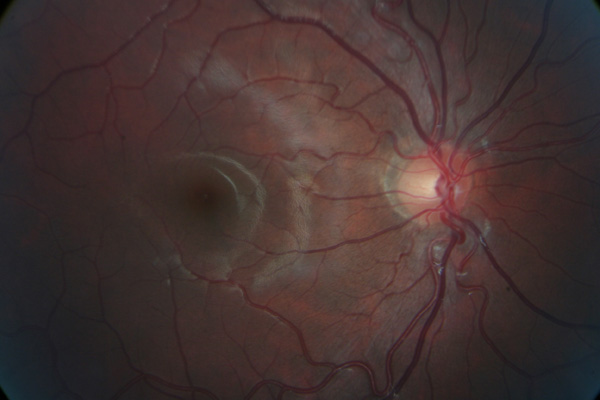

Retinal photos can assist in early detection of retinal problems like retinal detachment, holes or thinning, optic nerve disease, pre-cancerous lesions,

macular degeneration, hypertensive retinopathy, diabetic retinopathy, glaucoma changes and others.